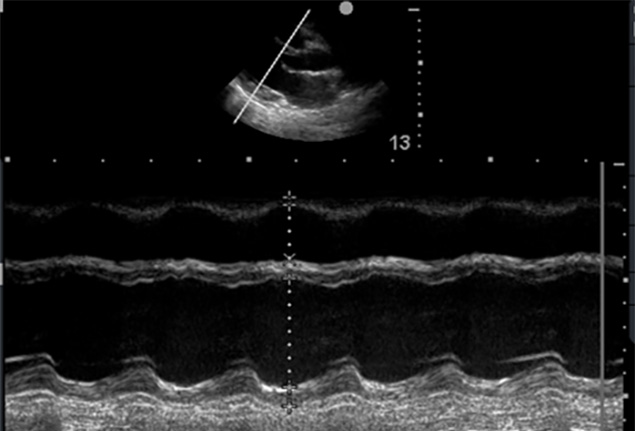

Cardiac Ultrasound

- Recap of core views

- Introduction to M-mode, colour and Doppler principles

- Qualitative assessment of left ventricular function

- Recognising basic valve pathology

- Basic right heart assessment

- Scanning protocol for shock and neonatal collapse

- Understanding when to escalate to formal echocardiography